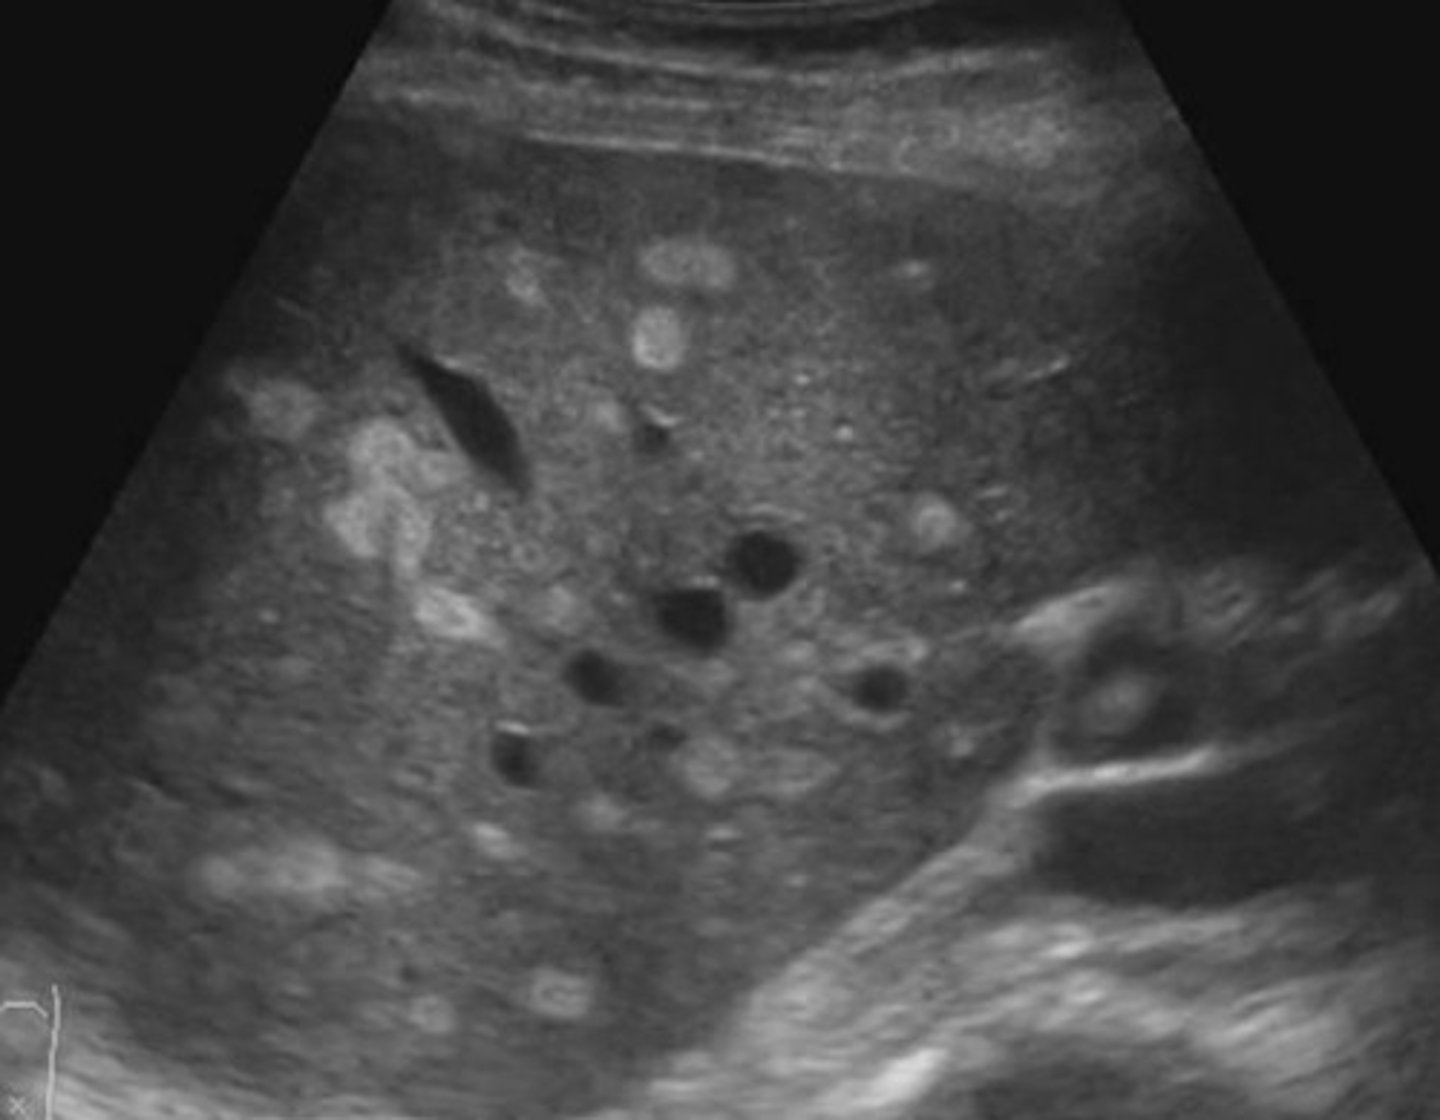

Abnormal = Hyperechoic areas are lipoma lesions in the liver

What is going on here? Is this normal or abnormal?